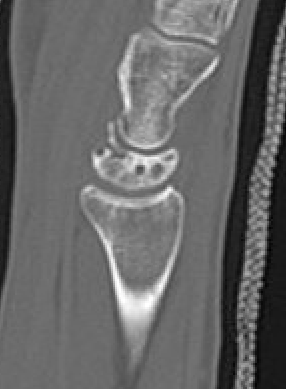

CT

Hesse et al J Hand Surg Eur 2025

- CT more accurate at gauging Kienbock's

- disease frequently worse on CT than assessed on xray

Lunate precollapse

CT demonstrating lunate fragmentation and collapse